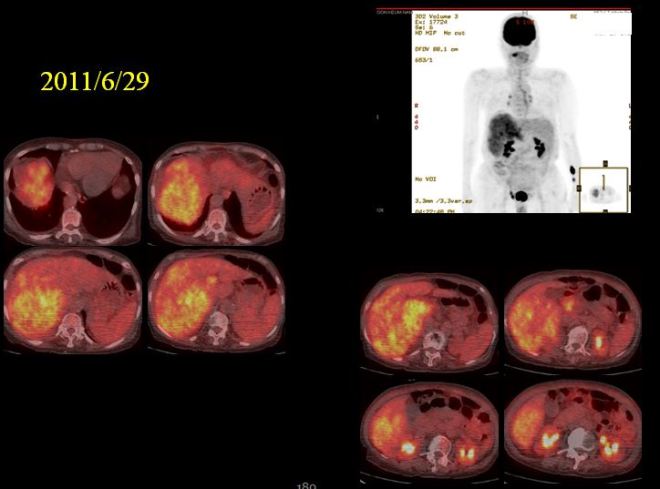

이 환자는 태음인으로 연세가 꽤 있는 분이었다. 간암 말기로 발견이 되어서 우측간엽이 거의 다 암으로 퍼져 있어서 색전술도 불가하고 넥사바를 사용하였다. 내가 보기로는 넥사바가 태음인 약물인데도 불구하고 피부에 대한 부작용이 너무 심해서 한 달도 채 못먹고 포기를 하였다. 일전에 소음인 환자가 넥사바를 항문까지 다 헐어가면서 복용하였는데 암이 매우 급속도로 자라서 전신에 퍼지고 눈까지 퍼진 경우를 보았다. 이후에 협진하는 병원의 선생님이 체질 분류를 원해서 몇몇 태음인들을 분류해 주었는데 넥사바 사용으로 매우 좋은 결과를 가져왔다는 이야기를 들었다. 하지만 이분은 피부 손발에 부작용이 심해서 사용치 못하고 중단하고 내원하였다.

위에서 보듯이 한 달여 넥사바 사용 후에 종양은 더욱 진전이 되고 손발의 허물은 다 벗겨졌다. 이분은 70세가 넘는 분이었고 당시 복수흉수가 모두 심하게 차 있어서 내 생각으로는 얼마 못 가시리라 생각하였다.

PET에서 보이듯이 우측 간엽은 모두가 암이었다. 그래서 보호자들에게 내 생각을 이야기하였다.”나이가 젊으면 한 번 시도해 보겠고 연장이 되시겠지만 현재 흉복수가 모두 차서 알부민도 맞아야 하고 병원에서 심하면 복수를 빼가면서 영양제 공급과 함께 병원을 들락날락 해야 되니 요새같이 바쁜 세상에 가족들도 힘들고, 노인도 오히려 빨리 돌아가시는 게 도와주는 길이라고 이야기 하였다. “환자들에게는 잔인한 이야기로 들릴 터이지만 삶의 질이라는 차원에서는 너무 힘든 일이라고 생각되었다. 한데 이가족 형제들은 우애가 놀랍고 두 분 다 대단한 효자였다. 어머니가 우리를 고생해서 키우느라고 얼마나 애쓰셨는데 우리 가족은 어머니에 대한 보답을 해야 한다면 아무리 힘들고 경제적으로 어려워도 최선을 다 해 보겠노라고 하였다. 환자는 체중도 많이 나가고 무릅도 약하고 비만이었고 일반인처럼 운동이나 여러 가지 다른 요법을 하지 못할 것 같아 보였다. 그래서 바로 위의 TDP를 하나 집에서 사 놓고 아침 저녁하시면서 한약을 들게 하였다. 양약은 어차피 태음인에 맞는 넥사바를 쓸 수가 없었기에 한약 단독으로 치료를 시작하였다. 그런데 이분은 놀랍게도 복수가 빠져서 무사히 3년 넘게 견디셨다.

사진에서 보듯이 간은 위축이 되었지만 커다란 종양은 거의 없어져서 일부분만 남아 있다. 당시 의무기록을 보면,

- 20130119-Gl/IR11087 [AC201 DP

- Abdominp-Pelvic C.T 이전 CT (2011-06-09)와 비교함.

- Liver에 최대 11 x 11 x 10cm의 multiple heterogeneously enhancing mass는 크게 감소하여 약 2.5 x 4.5 cm 으로 남아 있으며 right hepatic lobe의 atrophic change 있음.

- Main and right portal vein에 tumoral thrombosis 양 감소하였으나 남아 있으며

- portal vein은 more contraction 됨.

- Liver cirrhosis with splenomegaly 있음.

- Distal esophageal, paraesophageal, gastric fundal, and perisplenic varix 있음.

- Scanty amount of ascites 있음.

- [CONCLUSION]

- Marked decreased HCCs in right hepatic lobe

- Decreased amount of tumoral thrombosis in main & right portal vein

- Liver cirrhosis with splenomegaly, port。systemic collaterals, and scanty

- amount of ascites

“2011년 년 6월 9일과 2013년 1월 19일 CT 를 비교함. 간에 있던 최대 장경 11x11x10cm의 균일하지 않케 조영되는 암은 크게 감소하여서 2.5x 4.5로 줄어들었다. 우측간은 위축되어 있고, main과 우측의 portal vein의 종양에 의한 thrombosis 양이 줄어들었으나 남아 있고, portal vein (문맥)은 더욱 수축되어 있다. 간경화와 비장종대도 있다. 식도와 위장 부근의 비장 옆의 정맥류가 보이며 약간의 복수가 있다.”

18 개월만에 간의 종양이 거의 체적대비하여서 4% 정도로 줄어들었고 2014 년도 3월에 통합의학대회에서 본인이 강의하기 전에 환자에게 CT 를 찍어볼 것을 권유하였다. 이분은 광주분이라 거의 내원을 하지 않고 전화상담과 약물만 꾸준히 지어서 복용하였는데 만 3년이 넘은 2014년 봄에는 더욱더 종양이 줄어들었지만 부분적으로 재발소견을 보였다.